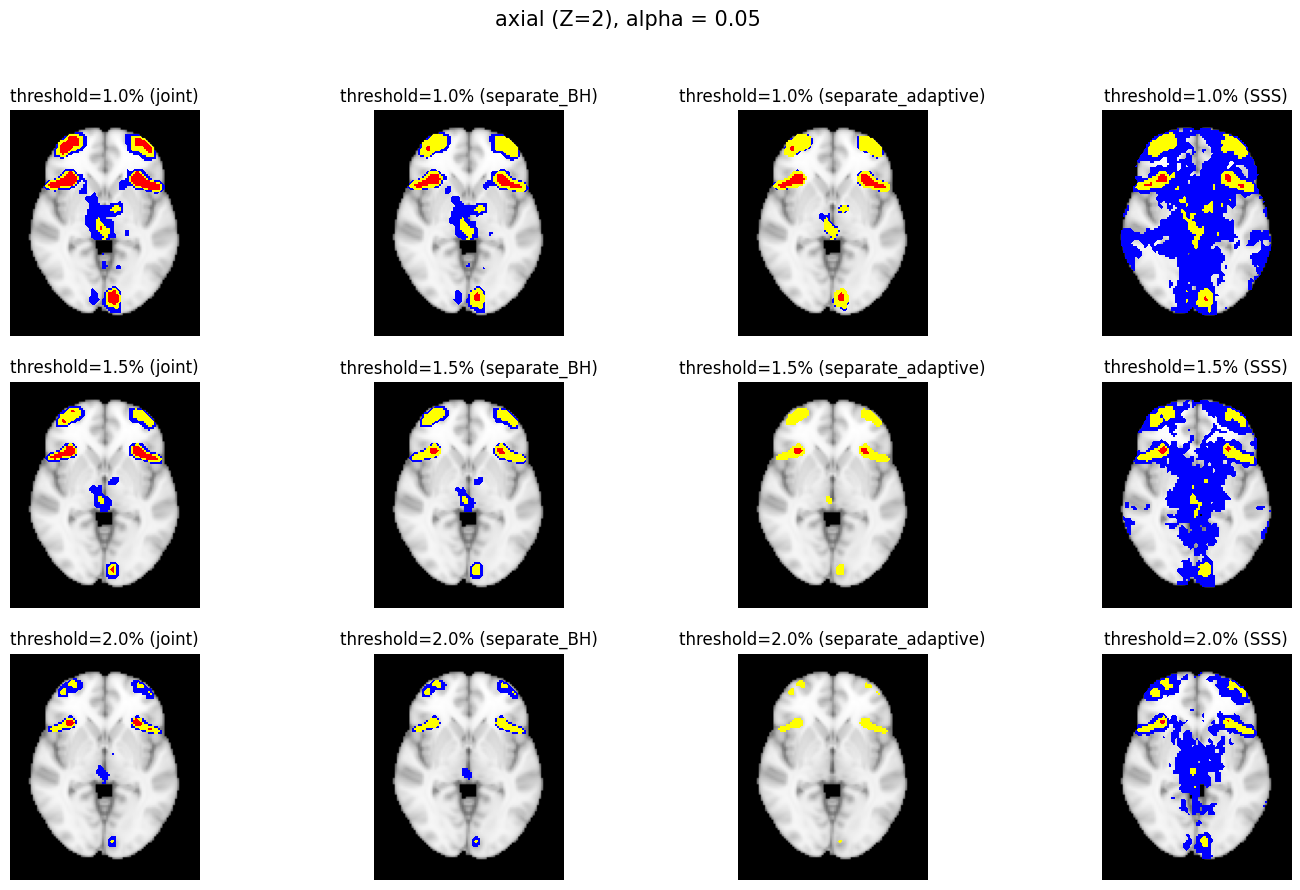

5.2 Confidence Region Result

The confidence regions are constructed on fMRI scans from 77 subjects as a real data application of the proposed methods after applying additional smoothing with Gaussian kernel with FWHM to match the results shown in Bowring (2019) [BOWRING2019116187]. Confidence regions using 1) the joint method with , 2) the separate method with BH adjustment for upper and lower side each with , 3) the separate method with BH adjustment for upper side and two-stage adaptive procedure for lower with , and 4) SSS () were compared with threshold level 1.0%, 1.5%, and 2.0% Blood Oxygenation Level Dependent (BOLD) change. Joint control confidence regions are produced with instead of 0.05 for the reasons mentioned in chapter 3.

For all slices, FDR controlling methods show tighter inference of both upper and lower CR compared to the SSS method. SSS shows smaller upper CR and larger lower CR which suggests more conservative inference compared to FDR controlling testing based methodologies. This is due to the fact that by controlling for FDR, the method allows for more false discoveries in exchange for more discoveries in general. Despite having higher level at , joint control confidence regions still show comparable results to other methods even with higher significance level. Naturally, as the threshold goes up, the area enclosed between the upper and lower confidence regions decreases.

Confidence regions with separate controls of FDR for lower and upper are presented in two forms for comparison: one with BH procedure for the lower confidence region, and the other one with the two-stage adaptive procedure for the lower confidence region. The upper confidence region remains the same as both methods uses BH procedure for the upper set FDR control. Lower confidence regions with adaptive method are smaller than lower sets with BH procedure which is to be expected as the two-stage adaptive procedure is less conservative when more voxels are thought to be rejected. In the context of negative one-sided testing, this is equivalent to when there are less number of voxels above than below .